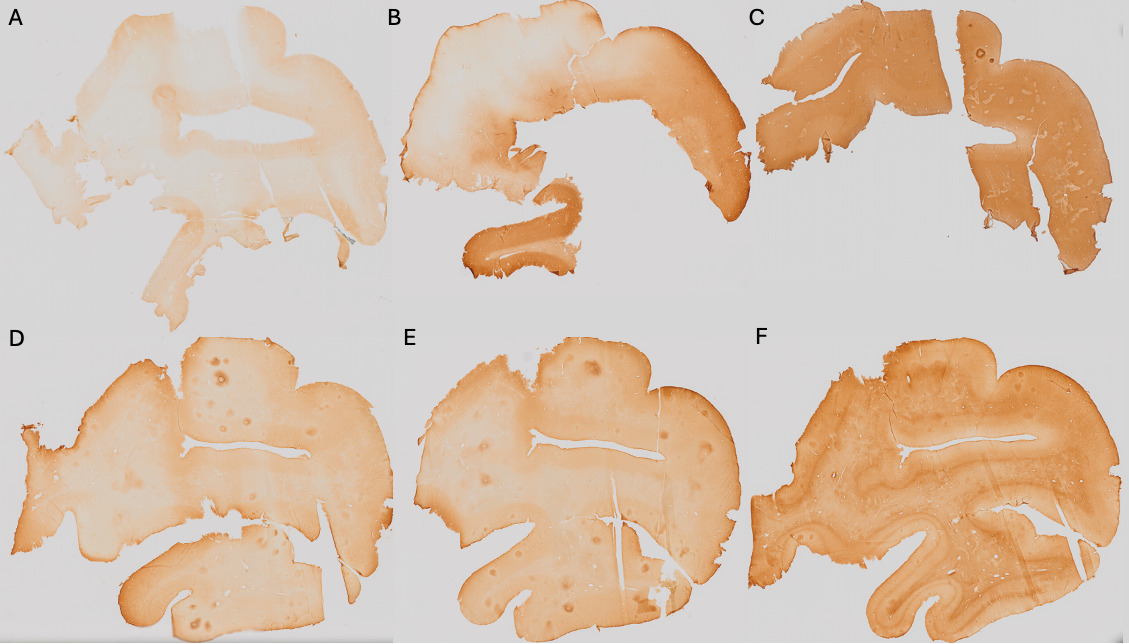

The number of tags used for manual registration was considered a variable reflecting the ease of registration. If more than 4 tags were needed (minimum to initiate manual alignment), this suggested a more complex registration. An example of the anatomical landmarks (6 tags) that were used is shown in Figure 2.

Figure 2.Process of the manual registration using landmarks.

A) Histology section. B) Native T2-TurboRARE MRI sequence. C) T2-TurboRARE MRI registered to the histology section. D) Overlap of the histology and registered MRI. Colored stars (6 tags in total: orange, red, blue, pink, yellow and green) show the landmarks that were used to initiate the registration between A and B, which resulted in C, and the overlap of both modalities in D.